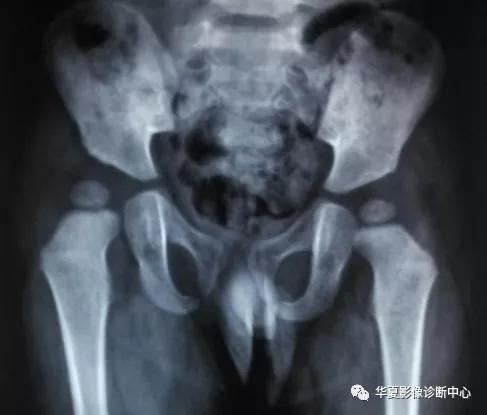

根据Growe分级标准,CDH可分为三期:Ⅰ期,脱位50%以下;Ⅱ期,脱位50%~70%;Ⅲ期,脱位75%~99%。

根据Zionts分级标准,CDH可分为四级(即四度):Ⅰ度为股骨头骺核位于两侧Y形软骨顶点的连线(即Y线)以下而在髋臼外上缘之外;Ⅱ度为股骨头骺核位于Y线与平行于Y线的臼上缘平行线之间;Ⅲ度为股骨头骺核位于臼上缘平行线高度;Ⅳ度为股骨头骺核位于臼上缘平行线以上,并有假臼形成。

临床上一般采用Zionts分级标准,其具有分类清楚、客观性强的优点,对于CDH患者的临床治疗具有十分重要的意义。